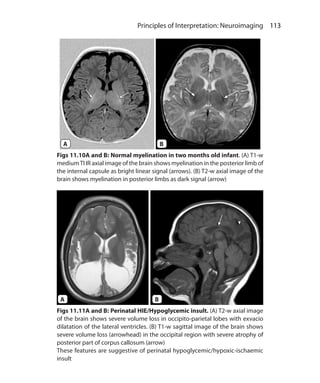

of tissues that uptake the contrast

5. Can be used in postcontrast imaging

required to null the signal from a tissue is 0.69 times T1 relaxation

time of that tissue.

Types of IR Sequences

IR sequences are divided based on the value of TI used. IR sequences